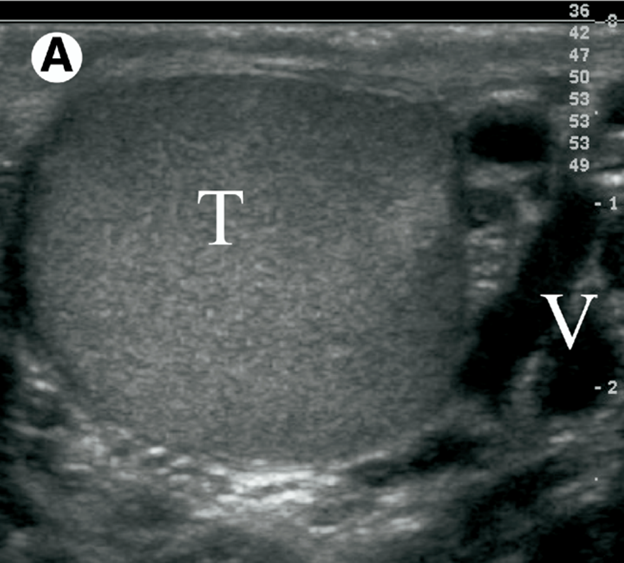

Acute-on-Chronic Events

Other scrotal conditions that are chronic in nature can also present with acute symptoms and include testicular neoplasms, spermatoceles and hydroceles. In the case of testis tumors, patients may only become aware of the mass after it has been present for many months, after it affects the appearance of the scrotum. However, testicular tumors can present precipitously if they undergo hemorrhage or necrosis, and produce swelling, pain and soreness. In this case, a scrotal physical examination reveals a firm, intratesticular mass and scrotal ultrasound demonstrates a solid intratesticular mass (which has a > 90% likelihood of being a germ cell tumor in adolescents and adults). The suspicion of tumor is important for the approach to exploratory surgery in the acute scrotum, as the correct surgical approach to testis cancer is through an inguinal incision and not transscrotally. In addition, the testis and its investments are dissected out intact, to minimize tumor spillage during surgery, and spermatic cord ligation is done in the inguinal region to further contain the spread of cancer (as lymphatic drainage of the testis and scrotum are different).

Other chronic scrotal lesions which can present acutely include hydroceles, spermatoceles and varicoceles. A hydrocele is characterized by increased fluid within the tunica vaginalis space (Figure 9). On physical exam, smooth scrotal swelling is present on inspection, and the testis is often unable to be palpated. A spermatocele is the cystic dilation of the fine ducts that lead from the rete testis to the epididymal head that can hemorrhage after trauma or become infected (Figure 10). On physical exam of a spermatocele, a smooth mass may be palpated superior or posterior to the testis. A scrotal varicocele is a condition characterized by dilated pampiniform plexus veins and that occurs in 15% of men at puberty, can be present for years but become acutely symptomatic (Figure 11). These dilated veins surround the spermatic cord and can present with a “bag of worms” appearance on visual inspection and texture on palpation. If the varicocele has acute onset, is only right-sided, or persists in the supine position, then retroperitoneal pathology must be excluded (i.e., IVC thrombus, abdominal mass, etc.). A careful history, physical examination and ultrasound examination is usually sufficient to diagnose these usually benign acute-on-chronic events. Urgent surgical intervention is rarely needed for drainage of a loculated infection or for a persistent hemorrhage associated with hydroceles or spermatoceles.

Figure 11 Testicular ultrasound of a varicocele (V) (From Pearl MS, Hill MC: Ultrasound of the Scrotum. Semin Ultrasound CT MR. (2007) 28:225-248.)